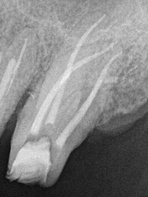

Es un procedimiento que

tiene como finalidad evitar la perdida del diente.

Para ello, se extrae la pulpa dental, se desinfecta y posteriormente se rellena y sella con material inerte y biocompatible.

¿Qué es una endodoncia?